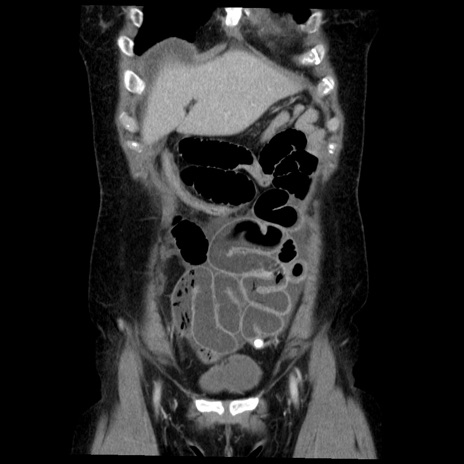

横断像

【症例】50歳代女性

【主訴】下腹部痛

【現病歴】本日朝より下痢2回あり。 昼食を食べた後、嘔吐3回、下腹部痛認め、症状軽快せず、当院救急搬送。

最終食事:本日昼(生ものなし)。 昨日の夜、刺身を食ぺたとのこと。周囲に同様の症状の者なし。普段、排便は毎日あるとのこと。

【既往歴】卵巣癌術後(8年前に当院で卵巣摘出)

【身体所見】 意識清明、腹部:平坦、腸蠕動音→、やや硬、下腹部自発痛・圧痛あり、反跳痛あり、筋性防御なし。

【データ】WBC 16000、CRP 0.01